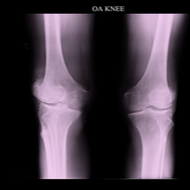

Osteopetrosis of marmerbeenziekte is een zeldzame erfelijke aandoening waarbij de aanmaak van het bot verstoord is.

Kenmerken zijn:

• dikke, broze botten die snel breken (misvormingen);

• groeiachterstand;

• bloedarmoede;

• vergroting van de lever en milt.